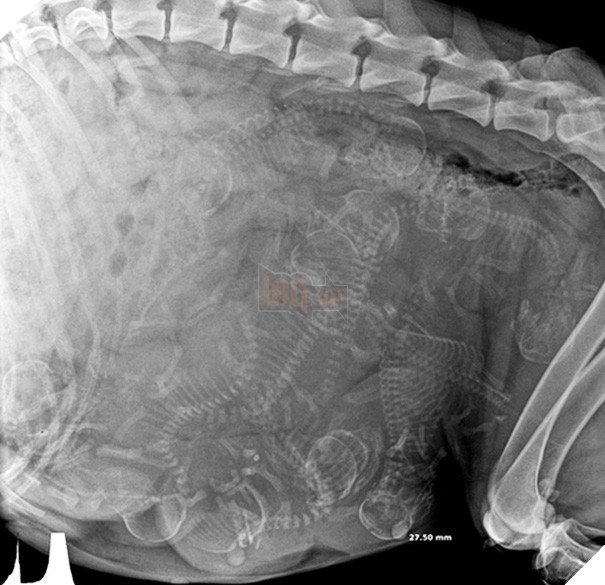

Trông có vẻ như các bé cún rất đông mà bụng chó mẹ thì lại chật hẹp. Thời gian thai của những chú cún hình thành và làm tổ ở sừng tử cung cho tới khi ra đời là khoảng 58 - 68 ngày (trung bình là 9 tuần). Những chú chó càng ít thai (dưới 4 con) thì thời gian mang thai càng dài.